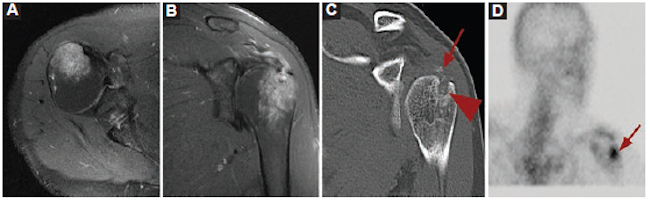

Varón de 16 años que consultó por un cuadro clínico de 3 días de evolución caracterizado por dolor, edema e impotencia funcional en el miembro inferior izquierdo, y fiebre. Como antecedente, había sufrido una caída de su propia altura realizando deporte. Se realizaron Rx y posteriormente RM, la cual informó una masa en el hueco poplíteo de características tumorales. Por su aspecto, el principal diagnóstico considerado fue el de fibromatosis agresiva. Se realizó punción-biopsia guiada por ecografía (Fig. 4).

Durante el procedimiento se evacuó contenido purulento y el resultado de la anatomía patológica informó un proceso inflamatorio agudo por Staphylococcus aureus resistente a la meticilina.